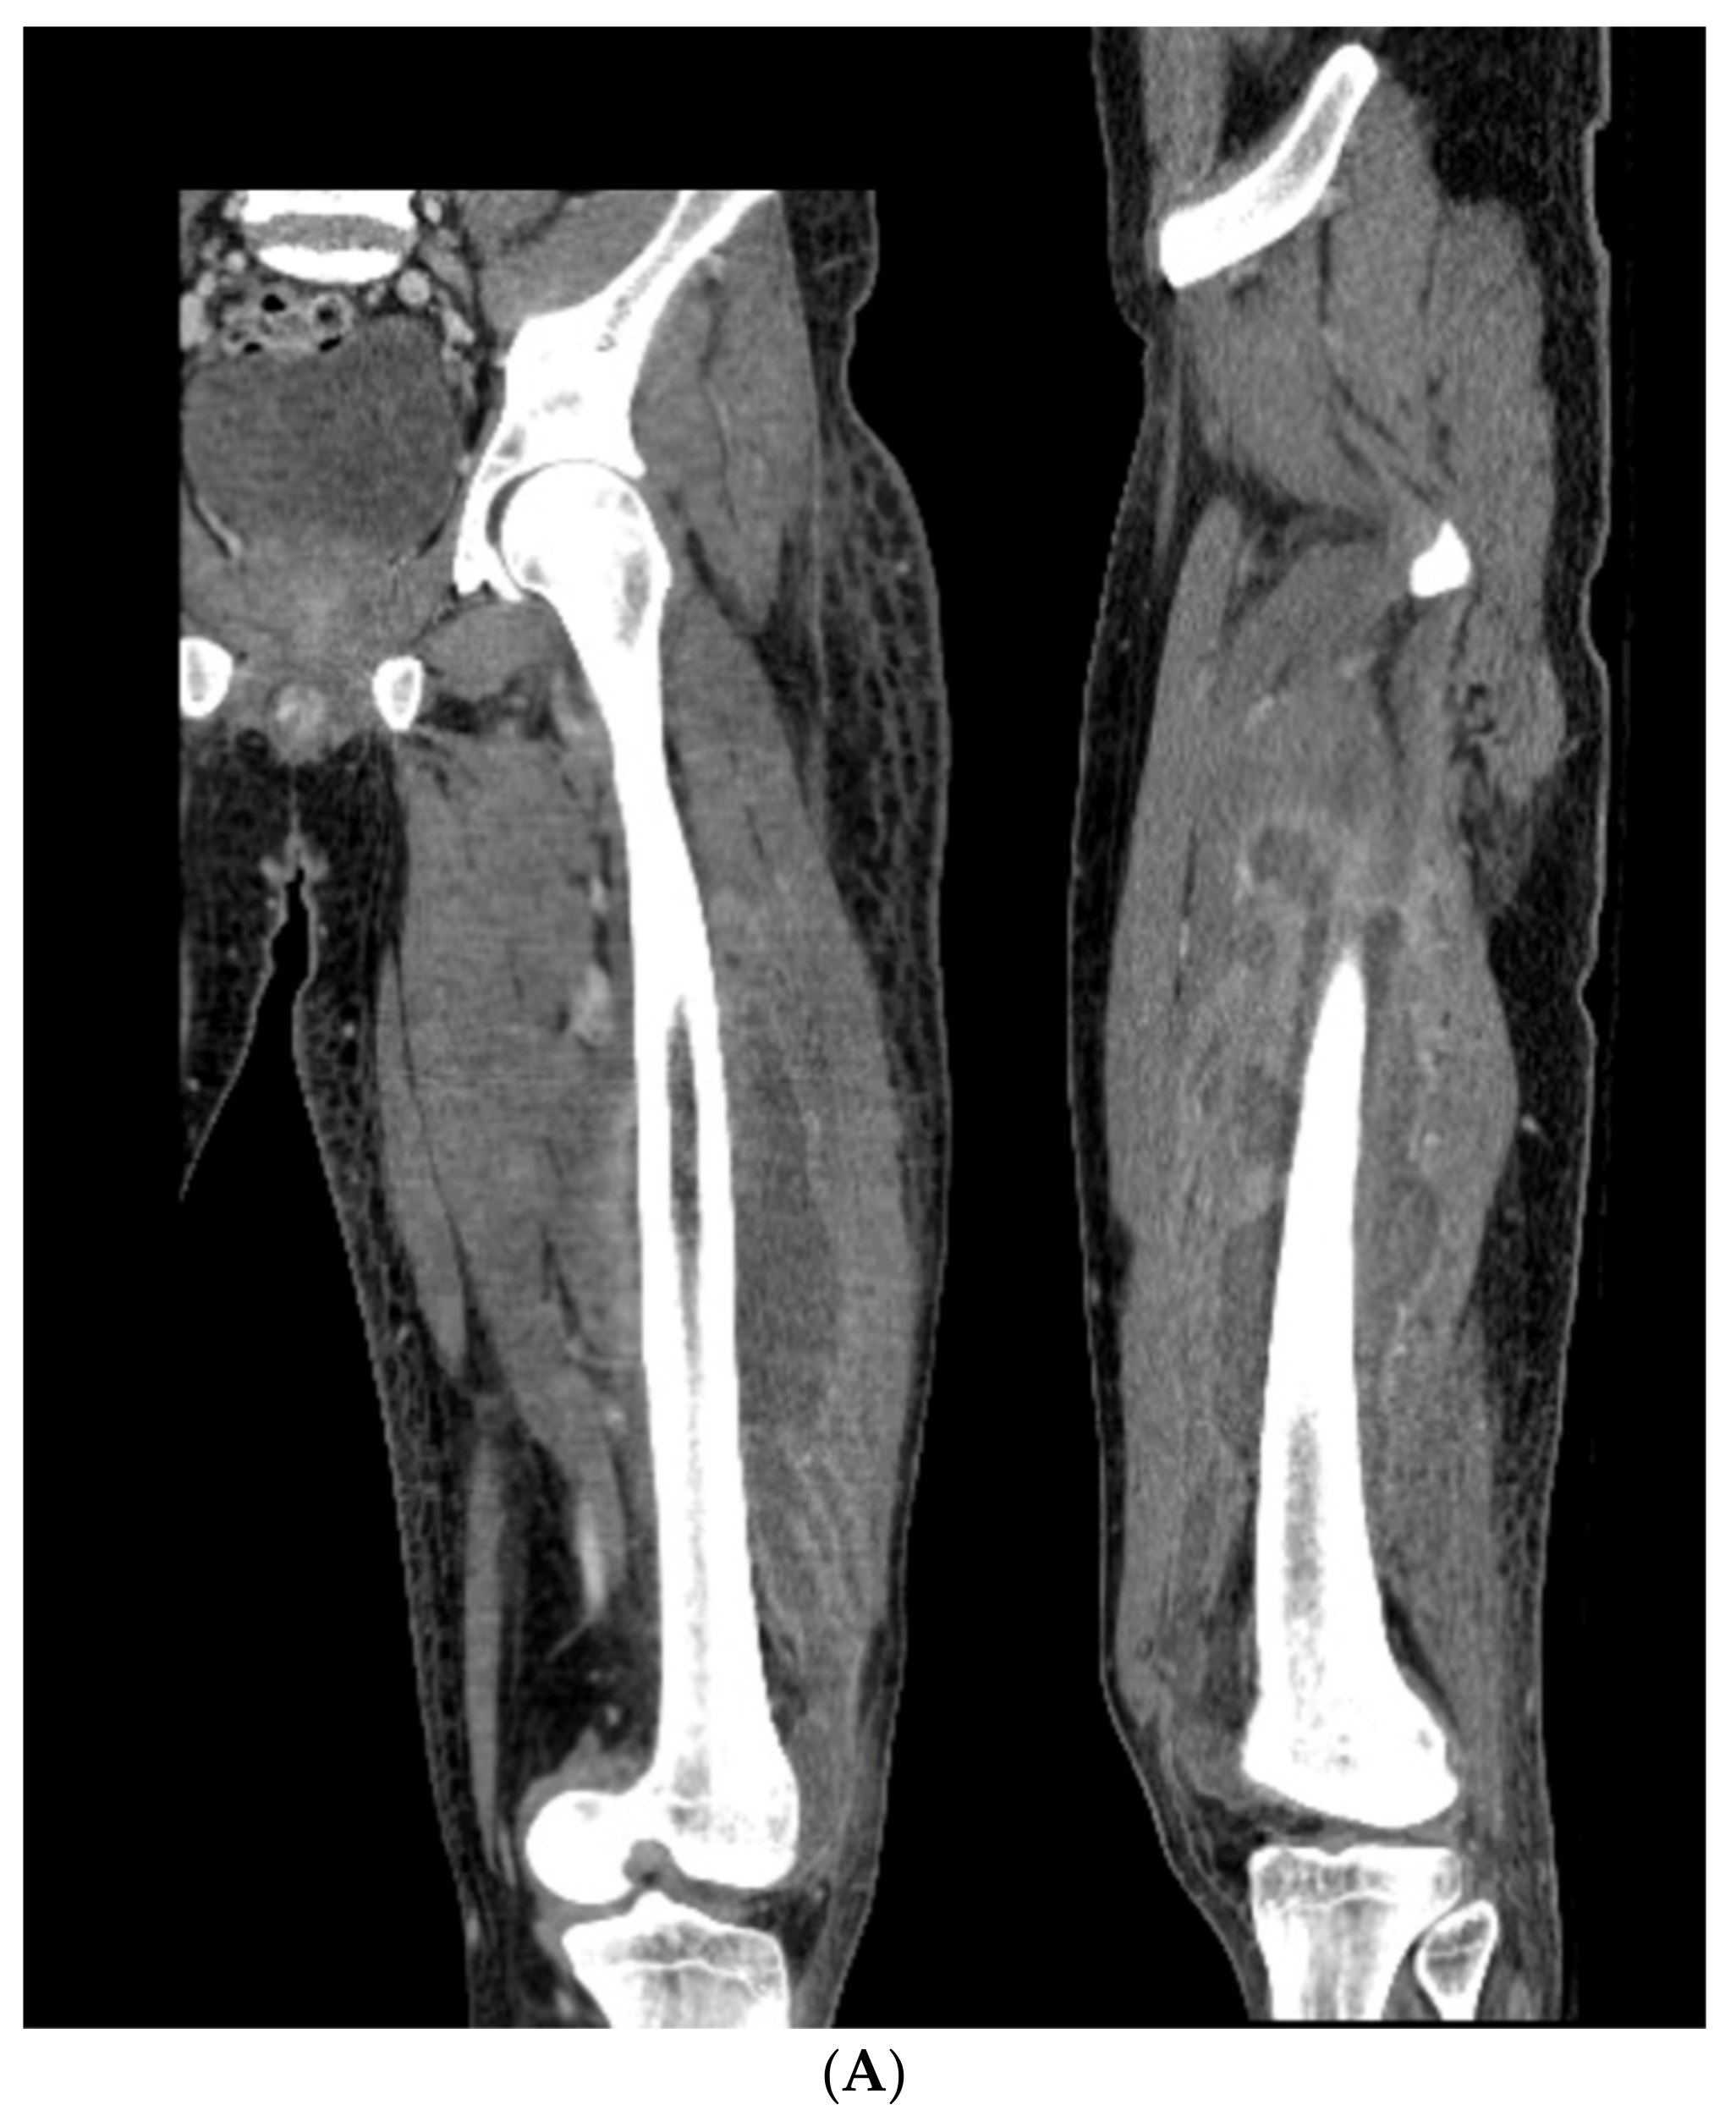

3.3. Case 3-Single-Plane Correction with Nail: Tibia

An adult male with no comorbidities presented with varus malunion following intramedullary tibial nailing, reporting symptomatic medial knee pain (Figure 8A). The CORA analysis revealed a varus deformity of 12 degrees. With a deformity in the coronal plane, surgical access was through an anterior approach using a focal dome osteotomy for correction. The anterior compartment was elevated, and a drill bit was placed in the CORA, with a parallel drill guide used to draw the arc with a second drill bit. The osteotomy was completed with an osteotome. The alignment was maintained during reaming using a temporary plate (Figure 8B). The patient underwent compression nailing using a magnetic motorized nail, allowing for subsequent compression as needed after discharge (Figure 8C). The patient felt pain-free at 12 weeks, yet was encouraged to return for regular follow-up examinations and X-rays until radiographic healing. Patient lost to follow-up after 6 months (Figure 8D).

Figure 8.

(A) Adult male with varus malunion deformity after a prior tibia fracture and nailing. (B,C) Patient underwent focal dome osteotomy with compression nailing using a magnetic motorized nail for early and subsequent nail compression. (D) Patient declined to follow-up after 12 weeks, citing absence of pain. Patient returned at 6 months at request of surgeon, still without pain. Magnetic nail recompressed. Patient lost to follow-up after 6 months.